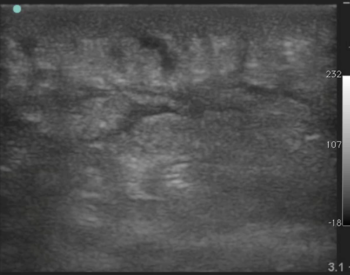

Cellulitis

Images

- Positive

- Cobblestoning - thin lines of fluid between fat globules

- Loss of tissue plain definition